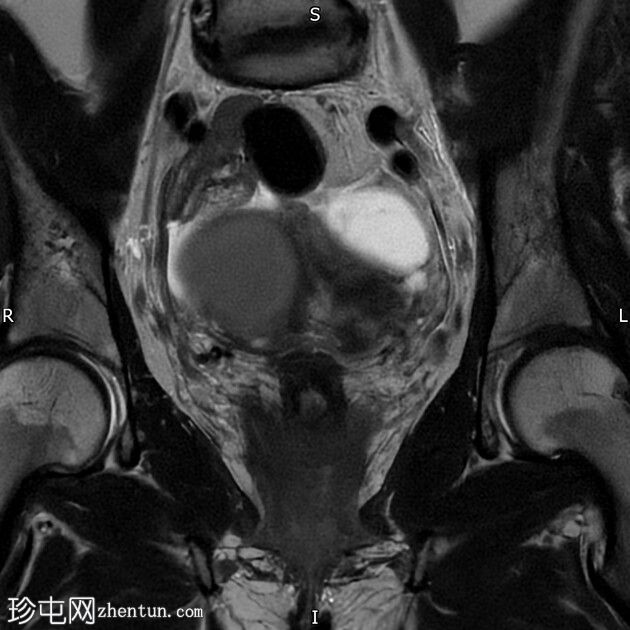

冠状位

T2加权像

右侧卵巢囊肿,T2加权像呈低信号,T1脂肪抑制像呈高信号,大小为6 x 5.2 cm,符合子宫内膜异位囊肿的影像学表现。

左侧卵巢囊肿,T2加权像呈低信号,T1脂肪抑制像呈高信号,符合子宫内膜异位囊肿的影像学表现。

双侧卵巢粘连于后道格拉斯窝,呈“接吻卵巢征”。

多发性子宫肌瘤。宫内放置宫内节育器。